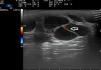

Ultrasound Imaging of Venous MalformationsVenous malformations typically present as anechoic or hypoechoic structures in B mode. Typically, venous malformations have scant fibrous stroma, but the walls of the isolated cavities range from very fine to very thick septa, and so up to 80% of these lesions have a mixed pattern of hypoechogenic cavities and hyperechogenic septa (Fig. 4),28 with the occasional presence of phleboliths.

At times, venous malformations are filled with thrombotic material. In these cases, the ultrasound image appears as a soft tissue tumor with mixed echogenicity, making it difficult to differentiate between hemangiomas and other soft tissue tumors (Table 3).29

In color Doppler mode, venous malformations have low and slow flows which are more marked with Valsalva maneuvers or compression-decompression. Venous malformations usually have a venous phasic spectrum with no arterial or arterialized venous flows within; these are more characteristic of arteriovenous malformations.